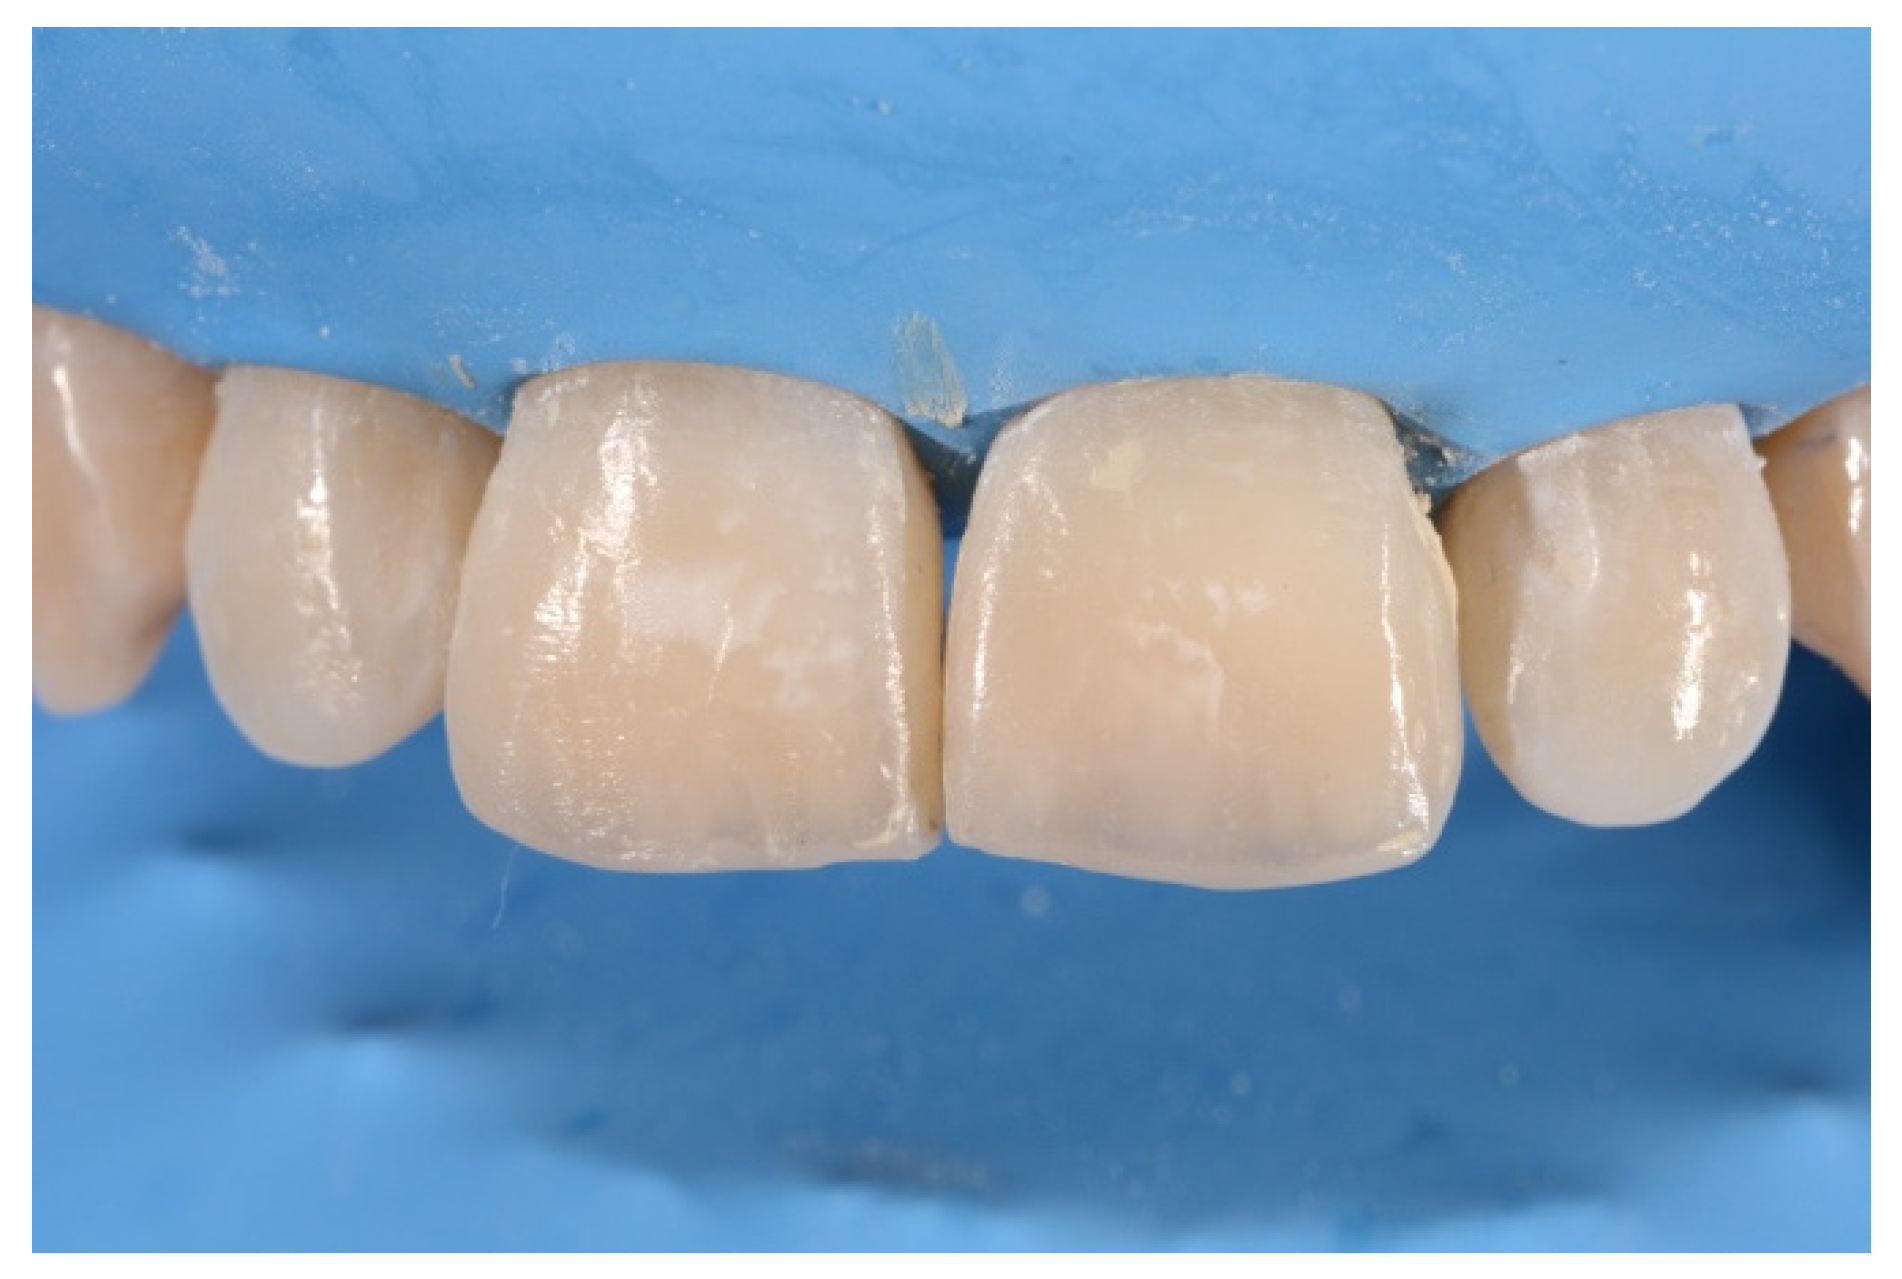

2. Case Presentation

- Molding palatal wall and incisal margin;

- Building interproximal walls with matrices;

- Layering free-hand buccal surface.